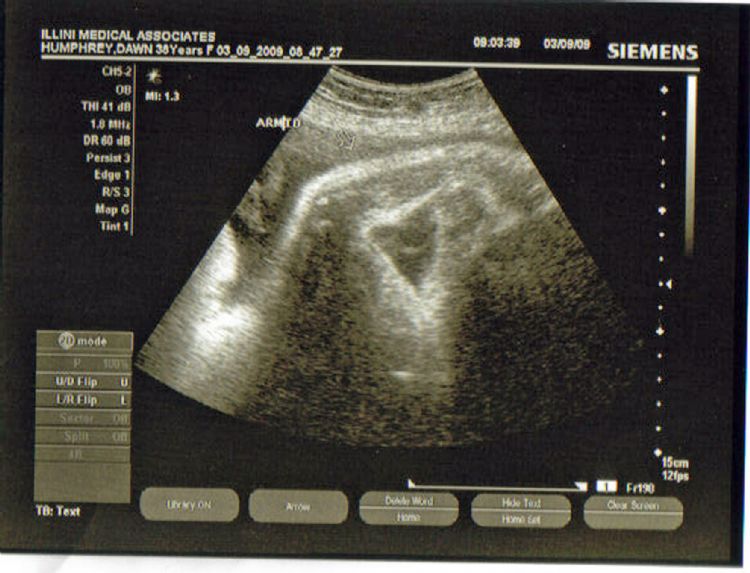

34.5 weeks - Gun Show

Here Erick flexes his arm and shows off his enormous bicep.